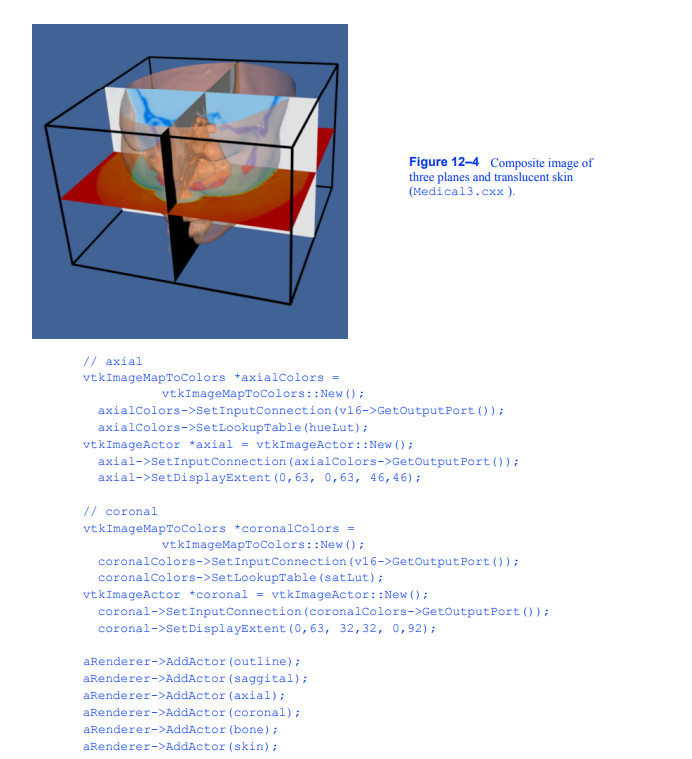

我们将提取三个正交平面,对应于放射科医生熟悉的轴向、矢状和冠状截面。轴向面垂直于患者颈部,矢状面从左到右,冠状面从前到后。为了便于说明,我们使用不同颜色的查找表来呈现每个平面。对于矢状面,我们使用灰度。冠状面和轴向面分别改变饱和度和色相表。我们将其与皮肤的半透明渲染相结合(我们使用c++语句bone- >VisibilityOff()关闭骨骼)。下面的VTK代码创建了纹理映射过程中使用的三个查找表。

使用筛选器vtkImageMapToColors结合上面创建的查找表将图像数据映射到颜色。切片的实际显示是使用vtkImageActor执行的(有关更多信息,请参阅第74页的“程序集和其他类型的vtkProp”)。这个类方便地将一个四边形、多边形平面与纹理映射结合在一起。vtkImageActor需要unsigned char类型的图像数据,类vtkImageMapToColors方便地提供了这种数据。为了避免复制数据并指定要使用的2D纹理,需要适当地设置每个vtkImageActor的DisplayExtent。c++代码如下:

合成图像如图12 - 4所示。在本例中,名为skin的参与者最后呈现,因为我们使用的是半透明表面。回想一下第213页的“透明度和Alpha值”,我们必须对多边形进行排序,图12-4三个平面和半透明皮肤的合成图像(Medical3。cxx)。12.2从分段的卷数据445中创建模型,组合透明表面以获得正确的结果。我们最后渲染皮肤,将其添加到aRenderer的演员列表中。